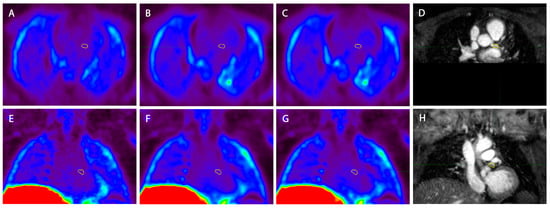

Molecular Imaging of Coronary Plaque Vulnerability Using 18F-Fluorocholine PET-MRI in Patients with Coronary Artery Disease: Validation with Optical Coherence Tomography

2.2. PET-MR Imaging

2.4. Image Reconstruction

2.5. Image Analysis